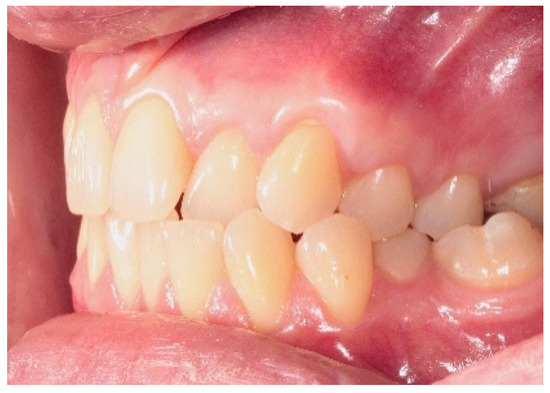

2.3. Surgical Procedures